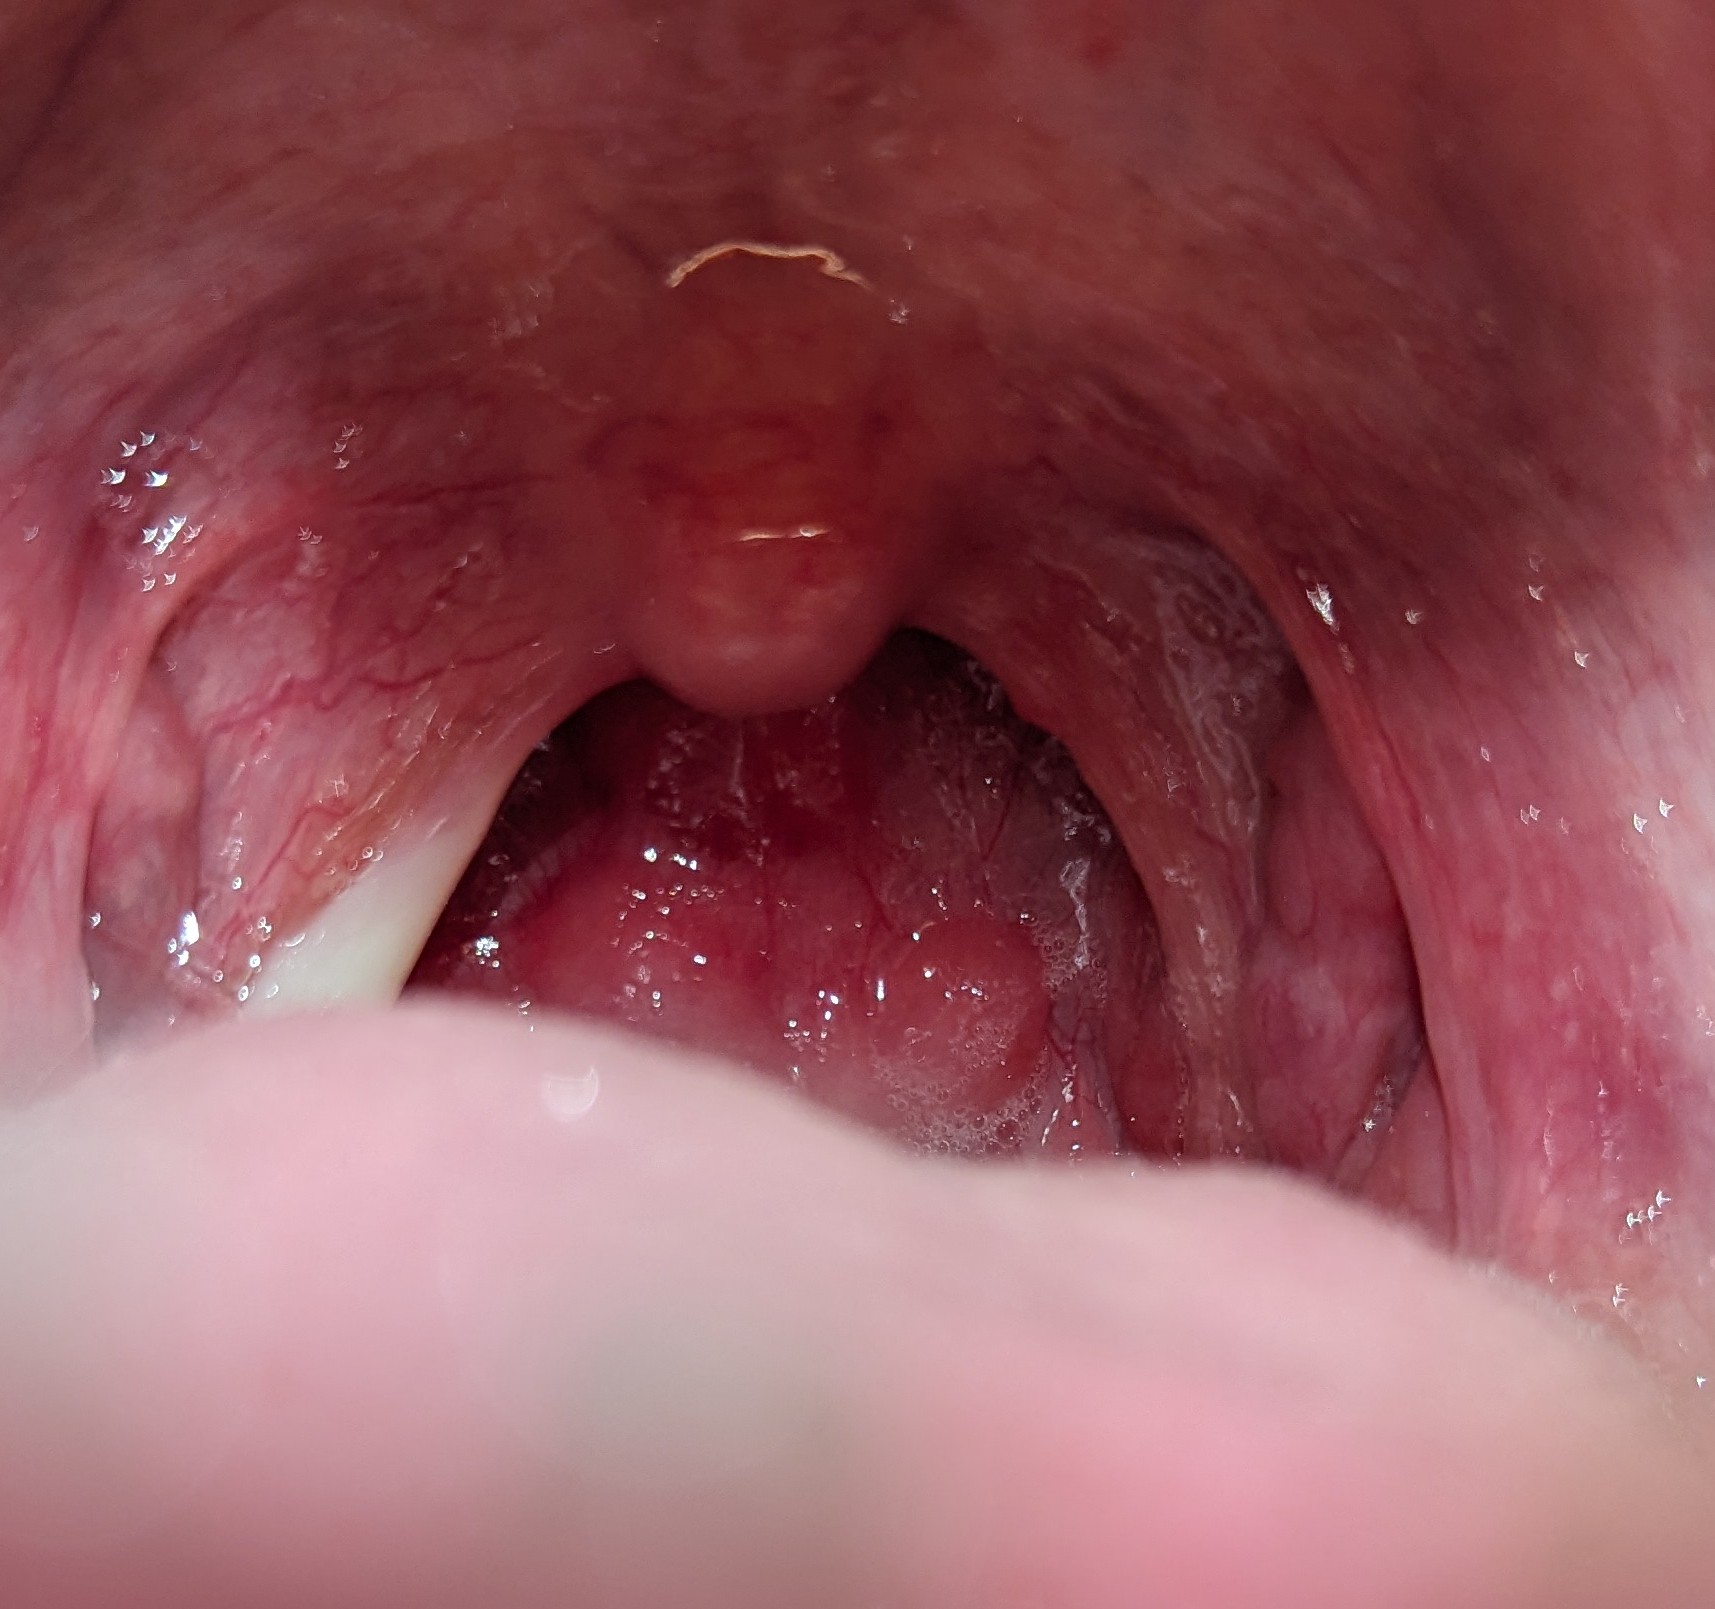

8 มิถุนายน 2567 18:59:59 #1 เริ่มจาก 7 วันที่แล้ว มีอาการน้ำมูกใสไหลทางจมูก จากนั้นเริ่มคัดจมูกและมีน้ำมูกและเสมหะเหลืองออกเขียว มีอาการอื่นร่วมด้วยได้แก่ เมื่อยตัว เหงื่อออกเหมือนคนเป็นไข้ แต่วัดอุณหภูมิแล้วไม่เกิน 37.5 ปวดหน่วงบริเวณหน้าผากและรอบดวงตา แสบและเจ็บคอกลืนน้ำลายแล้วรู้สึกเจ็บ และมีเสียงแหบเหมือนคนเป็นหวัด แต่ผ่านมาหลายวันอาการเหมือนจะดีขึ้น โดยในบางเวลาไม่มีน้ำมูกเลย จากนั้นกลับมามีซ้ำ ใสสลับเหลืองและหาย สลับไปมาจนถึงปัจจุบัน แต่เสียงยังแหบเหมือนคนเป็นหวัดเหมือนเดิม และมีเลือดปนออกทางจมูกเวลาสั่งน้ำมูกด้วย ปัจจุบันอาการที่มีตอนนี้ น้ำมูกและเสมหะยังมีเหลือง เหงื่อออก ปวดหน่วงบริเวณหน้าผากและรอบดวงตา รวมทั้ง แสบคอ พร้อมนี้ได้แนบภาพประกอบบริเวณคอมาให้คุณหมอพิจารณาด้วยครับ https://haamor.com/media/create_topic/20240608183656.jpg https://haamor.com/media/create_topic/20240608183708.jpg

11 มิถุนายน 2567 16:31:04 #2 น่าจะเป็นไข้หวัด คัดจมูกอยู่นาน จนมีไซนัสอักเสบแทรกซ้อนครับ

คอไม่ได้อักเสบคงจะเจ็บคอ

เพราะคัดจมูกและมีเสมหะติดเชื้อ

ไหลลงมาจากจมูกครับ